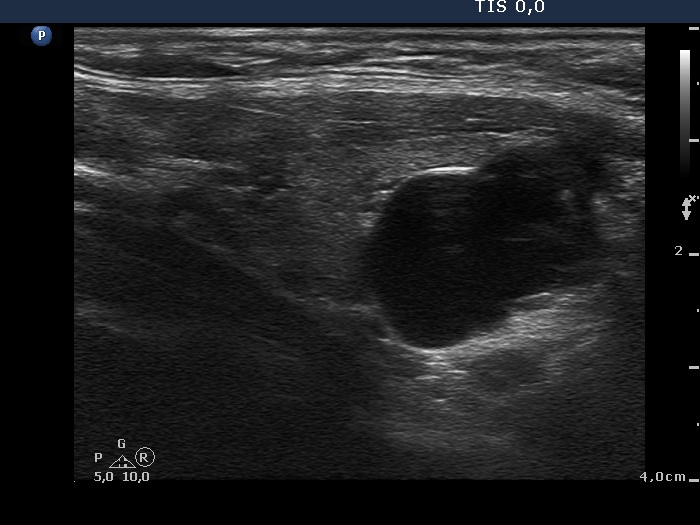

Ultrasonography: The thyroid was minimally-moderately hypoechogenic and presented fibrosis. There was a cystic lesion in the lower dorsal part of the right thyroid bed.

Twelve mL cystic fluid was aspirated. There were no cells on the smear.

Further laboratory tests aTPO 308 U/mL, calcium 2.25 mM/L, phosphorus 1.11 mM/L, parathormone 40.9 pg/mL (normal range: 10-65). The parathormone content of the cystic fluid was 383 pg/mL.